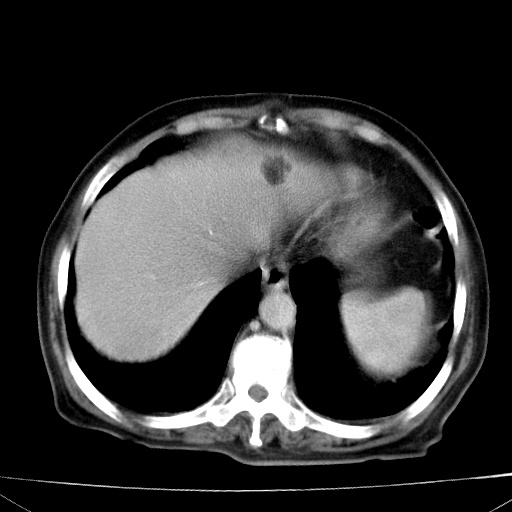

网站人气太旺!昨天的帖子就沉到海底,只好再发贴!ct18338:女 78岁,肝胆病变,已增强,再会诊!原帖链接:http://www.radida.com/bbs/forum.php?mod=viewthread&tid=50032

1)考虑胆囊癌侵犯肝脏并肝门区、腹膜后及右侧膈角后淋巴结转移。2)肝左叶近肝顶部囊肿。3)肝左叶肝内胆管结石。4)左肾近下极囊肿。

1、胆囊癌侵犯肝脏并腹腔及腹膜后淋巴结转移。

2、肝左叶外侧段囊肿。